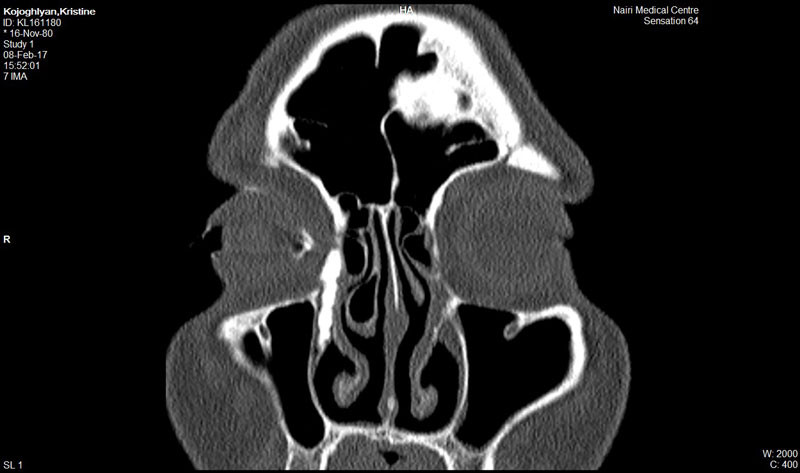

Հայաստանում միայն «Նաիրի» ԲԿ-ի Աչքի կլինիկայում է կոնտրաստային դակրիոգրաֆիա կոչվող ինովացիոն մեթոդով ճշգրիտ որոշվում արցունքատար խողովակների նեղացման տեղադրությունը եւ աստիճանը: